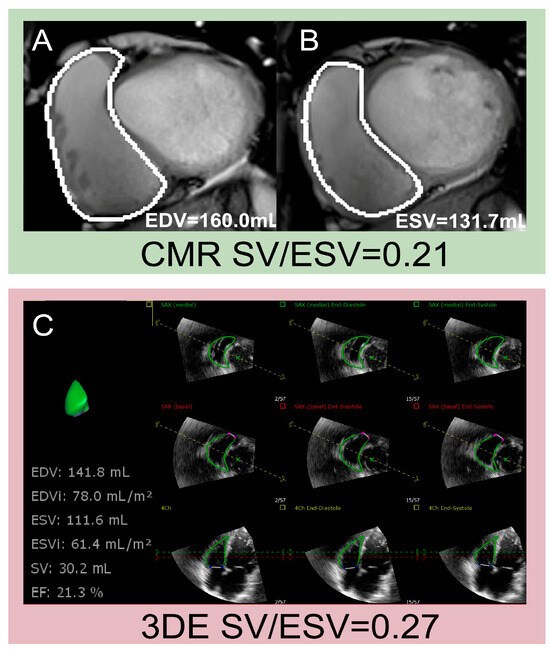

| Vîjîiac et al. [88] | 2022 | 139 | SV/ESV | SV/ESV < 0.54 | - | 3D SV/ESV was an independent correlate of severe HF symptoms in patients with DCM, and the cutoff value was 0.54 for predicting severely symptomatic status, which might be a useful risk stratification tool for these patients. |